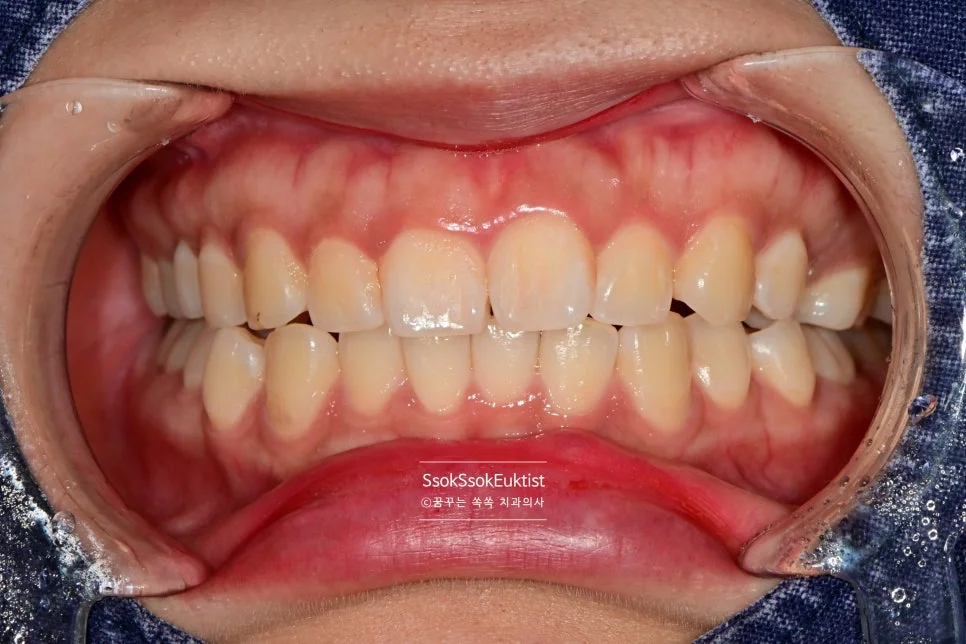

수면 스케일링 후 깨끗한 치아

After — 수면 스케일링 후

왼쪽 위 치경부 우식을 레진으로 예쁘게 치료한 후 스케일링도 시행하였는데요. 비교적 깨끗하고 건강해진 모습이 보입니다~^^